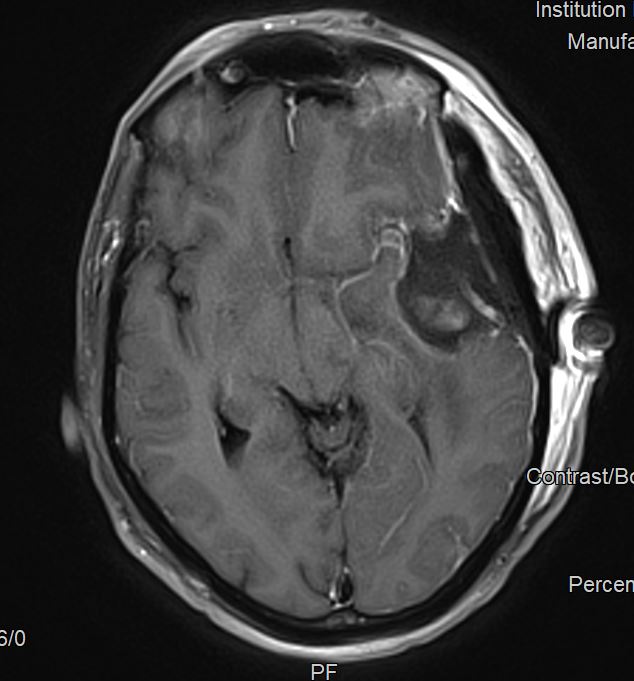

Η μετεγχειρητική μαγνητική τομογραφία ανέδειξε πλήρη εξαίρεση του όγκου.

Η μετεγχειρητική πορεία του ασθενούς ήταν ανεπίπλεκτη με πλήρη αποκατάσταση των συμπτωμάτων και ο ασθενής εξήλθε την 4η μετεγχειρητική ημέρα.